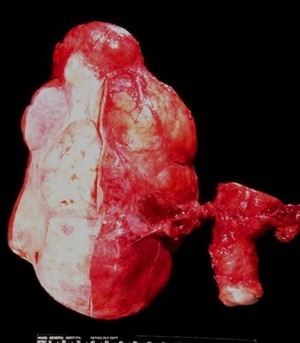

Below is a sample from the ovary of a 60 year old woman with no children and a family history of breast cancer (sister at age 45, mother at 53). What is the abnormality below and what is the prognosis?

Serous cystadenocarcinoma